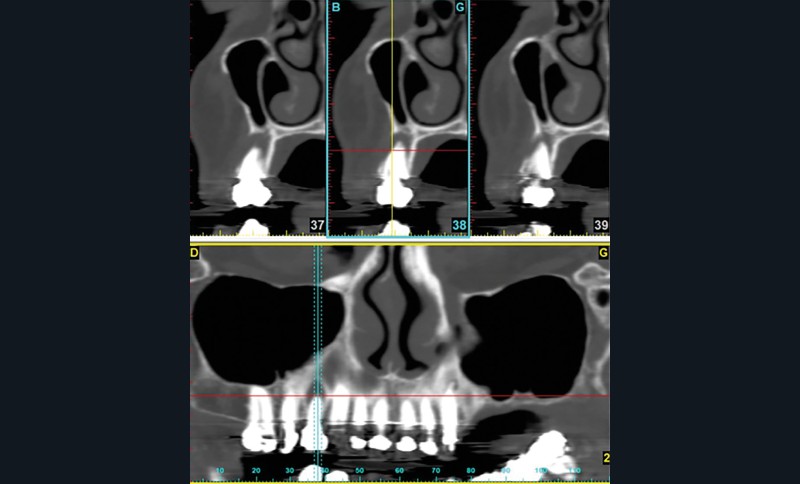

Contexte malin

Un examen clinique attentif prenant en compte les facteurs de risques carieux et parodontaux (contrôle de plaque, tabagisme en particulier) sera réalisé. Un bilan radiographique de première intention sera également nécessaire. A minima, la radio panoramique est indispensable. Elle sera complétée éventuellement par des clichés rétro-alvéolaires. En cas de doute, sur un foyer infectieux chronique péri-apical notamment, ces examens devront être complétés par un bilan d’imagerie tridimensionnel de type scanner ou CBCT. Les lésions de ce type, dans les régions sous-sinusiennes en particulier, sont difficiles d’accès à l’imagerie standard (fig. 1).